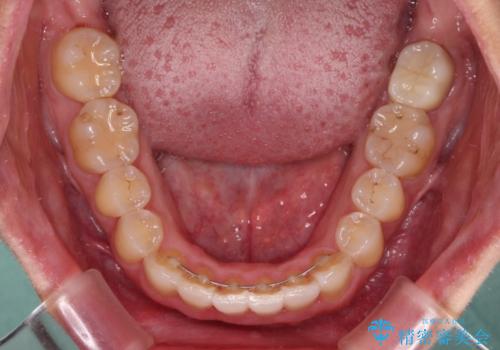

前歯のデコボコをインビザラインでスッキリと仕上げる

長時間のマウスピース装着に協力いただき、自然な口元に仕上げることができました。

気になっていた銀歯もオールセラミッククラウンで本物の歯のようになり、患者様には大変満足していただきました。